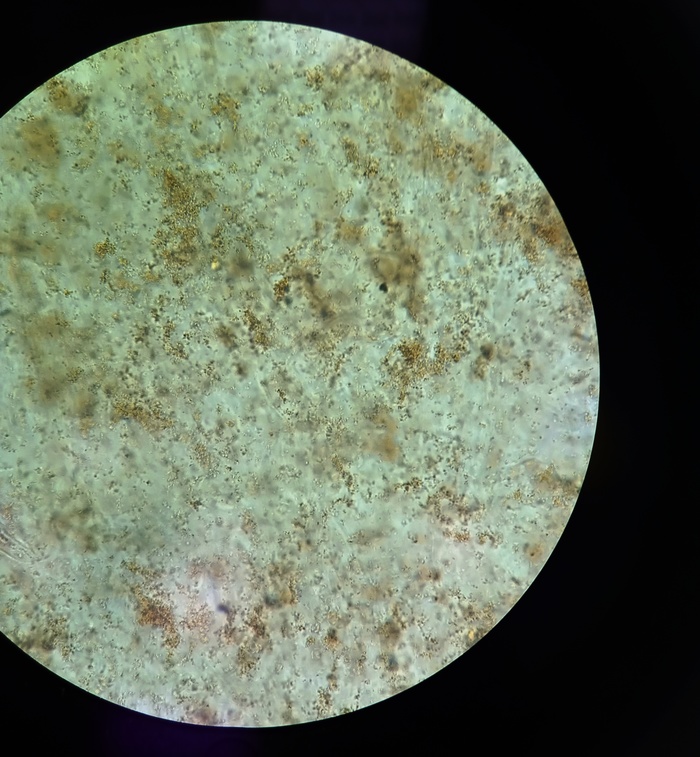

Ретикулоциты

Ретикулоциты – молодые красные кровяные клетки (эритроциты). Они образуются в костном мозге, когда стволовые клетки дифференцируются и делятся, превращаясь во взрослые эритроциты через стадию ретикулоцитов, постепенно теряя ядро и уменьшаясь в размере.

Большинство эритроцитов уже полностью созревшие, когда они покидают костный мозг и выходят в кровяное русло, однако 0,5-2 % из всех циркулирующих в крови – это ретикулоциты, которые превращаются во взрослые эритроциты в течение двух дней. Данный анализ показывает число и процент ретикулоцитов в крови и выявляет адекватность производства эритроцитов костным мозгом и степень его активности.